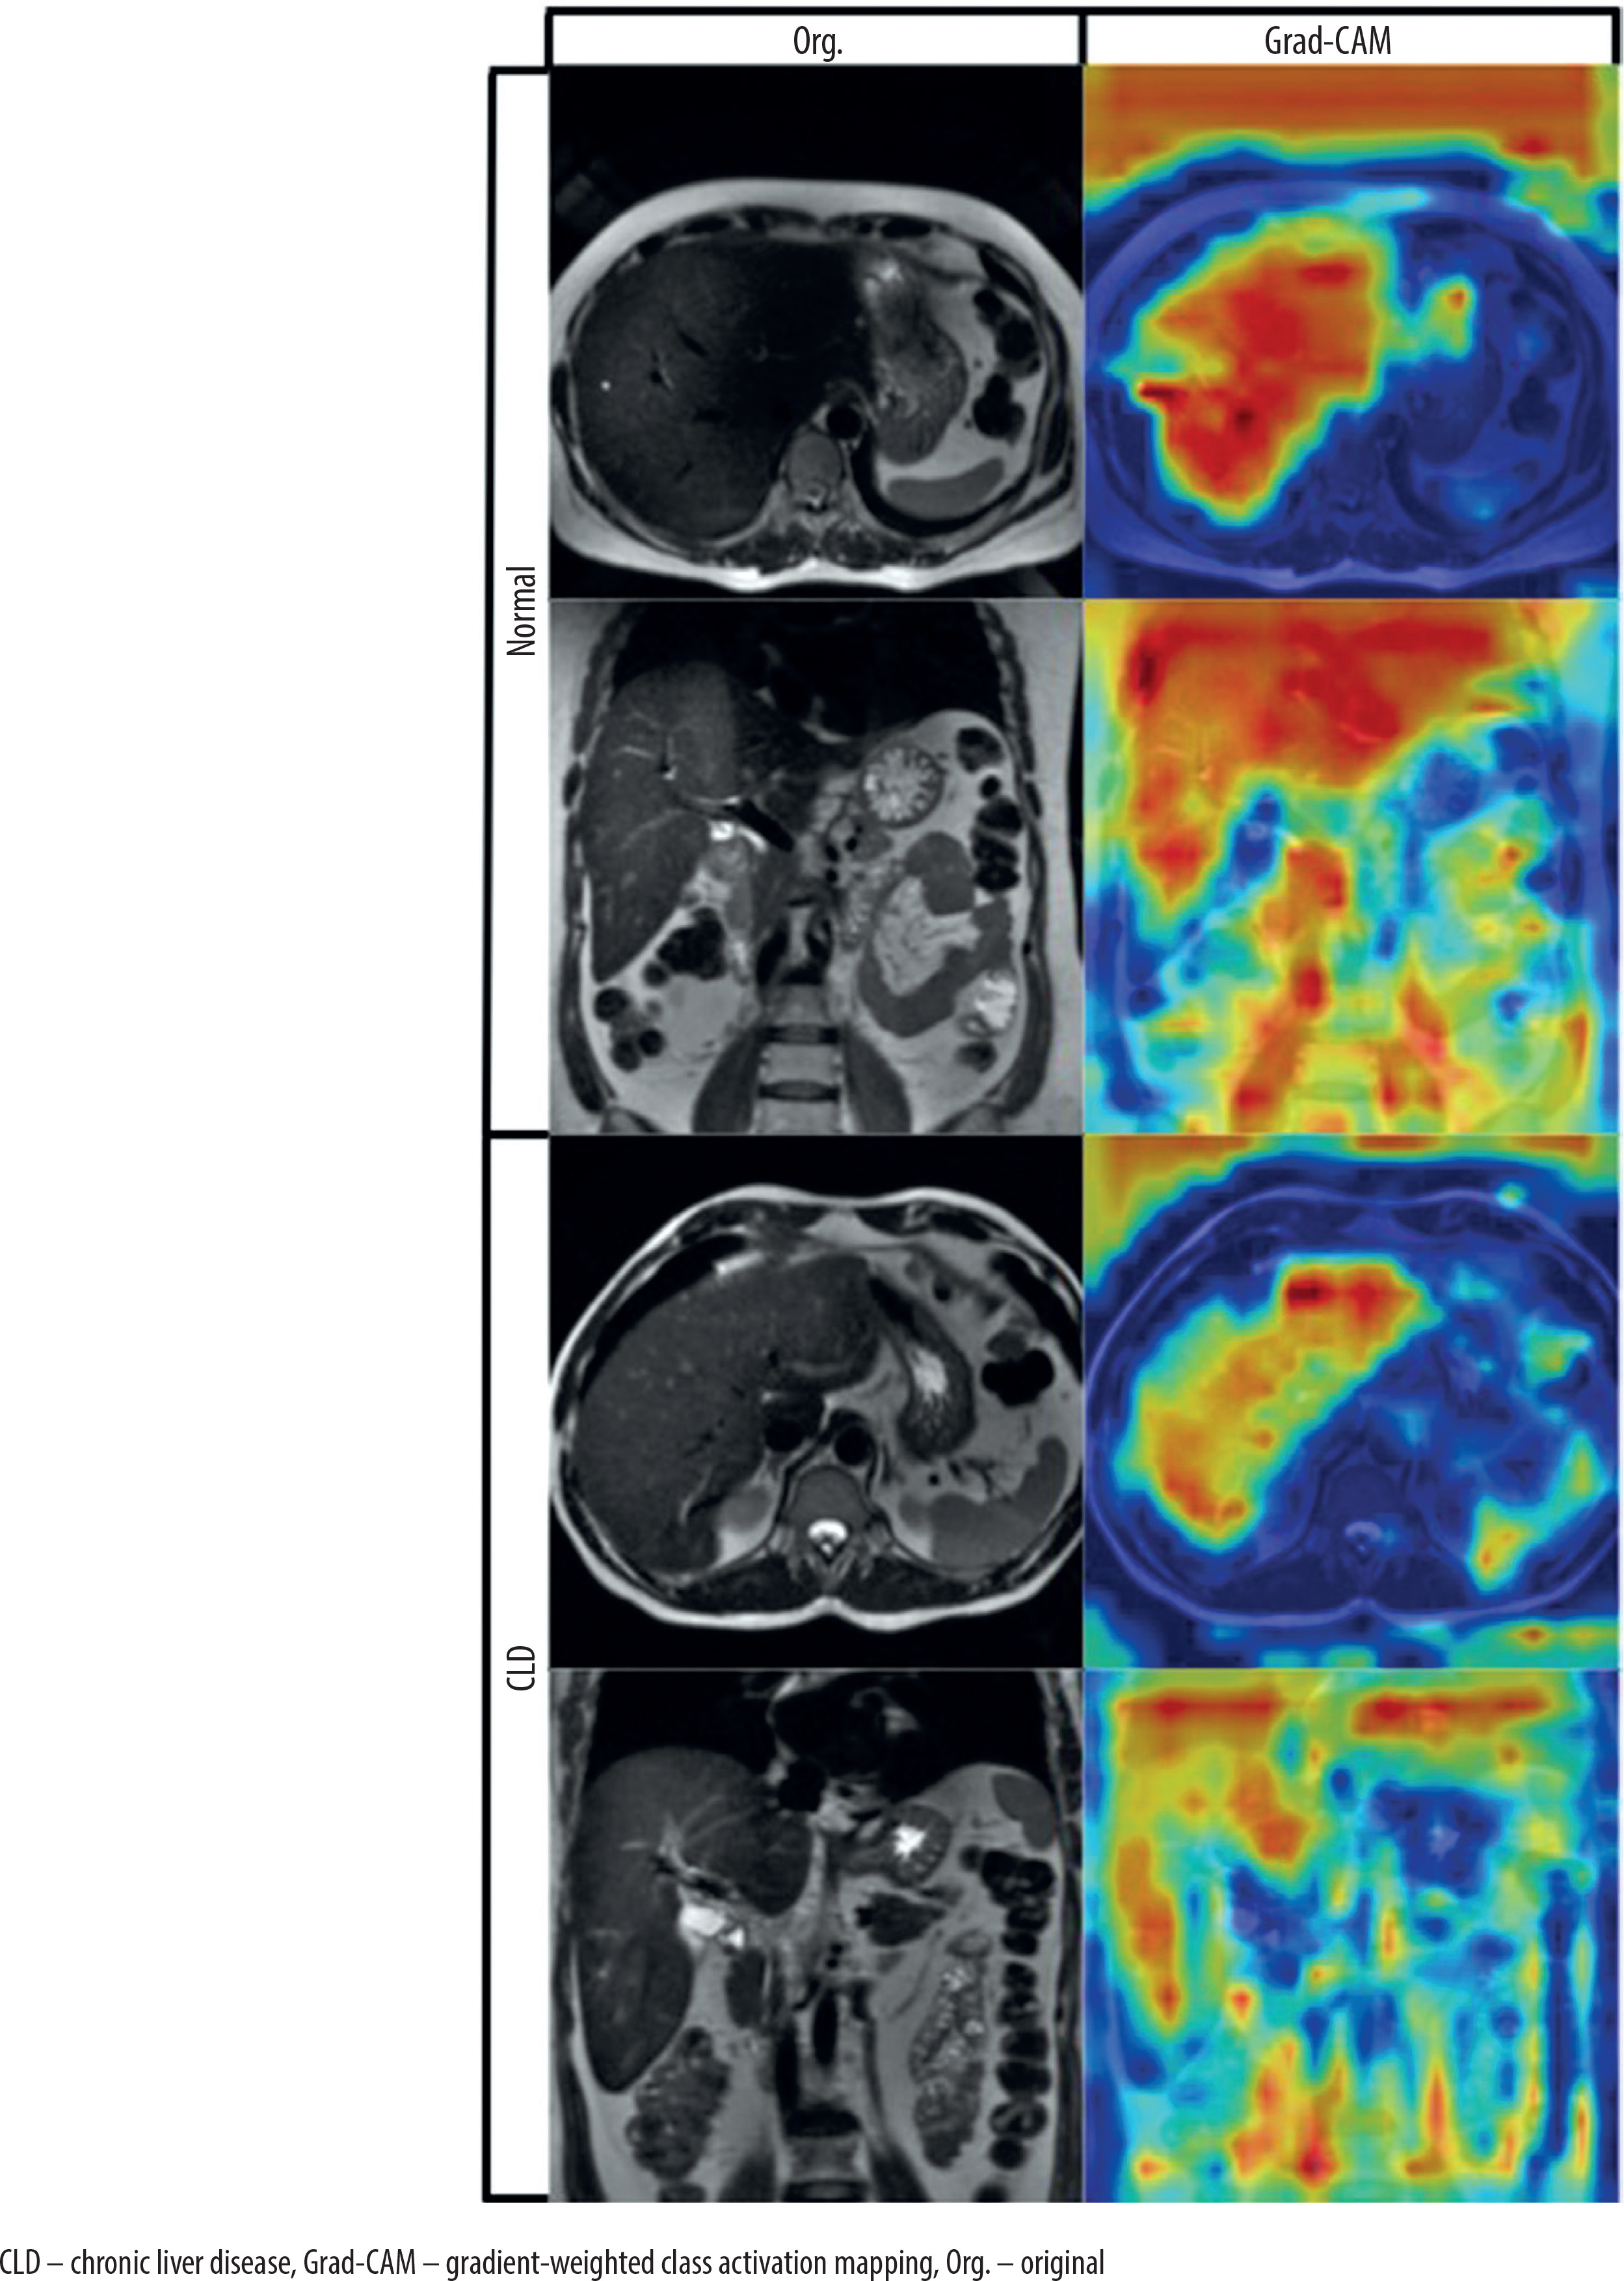

Explainability analysis

To interpret the model’s decision-making process, we applied gradient-weighted class activation mapping (Grad-CAM) to visualize the discriminative regions used by the DeepCNN model during prediction [23]. Grad-CAM is a widely used explainability technique that generates visual heatmaps highlighting the areas of an image that most influence a model’s prediction. It works by computing the gradient of the predicted class score with respect to the feature maps of a chosen convolutional layer, then weighting and combining these maps to produce a coarse localization map. In our case, Grad-CAM was applied to the final convolutional layer (Conv4), enabling us to observe where the model was focusing during classification. Representative examples of real CLD and normal cases are shown in Figure 3 to illustrate the behavior of the model.

To better understand the model’s decision-making process, Grad-CAM visualizations are presented in Figure 3. Grad-CAM is an explainability technique that highlights the regions within an image that most influence the model’s prediction by combining the final convolutional layer’s feature maps with the corresponding gradients. Across both axial and coronal views, and for both cirrhotic and normal cases, the model was observed to focus primarily on anatomically relevant regions, particularly within or near the liver parenchyma. While minor activations outside the liver were occasionally present, these did not have a significant impact on model performance. Considering that segmentation is a time-intensive and expertise-dependent task, the ability of the model to extract meaningful features from unsegmented raw images enhances its practicality and generalizability in clinical applications.

Grad-CAM analysis provided further validation for the segmentation-free approach, showing that the model was capable of attending to liver-relevant regions without requiring manual delineation. This enhances the interpretability and clinical trustworthiness of the model.